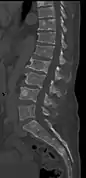

Illustration showing the most common site of bone lesions in vertebrae

Bone pain affects almost 70% of people with multiple myeloma and is one of the most common symptoms.[2]:653[22] Myeloma bone pain usually involves the spine and ribs, and worsens with activity. Persistent, localized pain may indicate a pathological bone fracture. Involvement of the vertebrae may lead to spinal cord compression or kyphosis. Myeloma bone disease is due to the overexpression of receptor activator for nuclear factor κ B ligand (RANKL) by bone marrow stroma. RANKL activates osteoclasts, which resorb bone. The resultant bone lesions are lytic (cause breakdown) in nature, and are best seen in plain radiographs, which may show "punched-out" resorptive lesions (including the "raindrop" appearance of the skull on radiography). The breakdown of bone also leads to the release of calcium ions into the blood, leading to hypercalcemia and its associated symptoms.[23]

The diagnostic examination of a person with suspected multiple myeloma typically includes a skeletal survey. This is a series of X-rays of the skull, axial skeleton, and proximal long bones. Myeloma activity sometimes appears as "lytic lesions" (with local disappearance of normal bone due to resorption) or as "punched-out lesions" on the skull X-ray ("raindrop skull"). Lesions may also be sclerotic, which is seen as radiodense.[70] Overall, the radiodensity of myeloma is between −30 and 120 Hounsfield units (HU).[71] Magnetic resonance imaging is more sensitive than simple X-rays in the detection of lytic lesions, and may supersede a skeletal survey, especially when vertebral disease is suspected. Occasionally, a CT scan is performed to measure the size of soft-tissue plasmacytomas. Nuclear Medicine Bone scans are typically not of any additional value in the workup of people with myeloma (no new bone formation; lytic lesions not well visualized on nuclear bone scan).